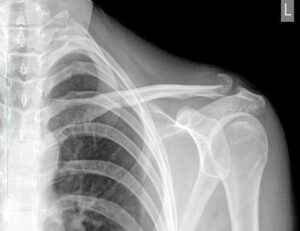

Перелом тазобедренного сустава

Перелом бедра — одна из самых серьезных травм, диагностируемых у подавляющего большинства пожилых людей. Из-за сложной структуры и потери прочности кости заживают медленно и требуют длительной реабилитации. Опасность такого типа перелома заключается в риске развития различных осложнений. Анатомия тазобедренного сустава Тазобедренный сустав имеет сферическую форму и соединяет бедренную кость с вертлужной впадиной тазовой кости. В …